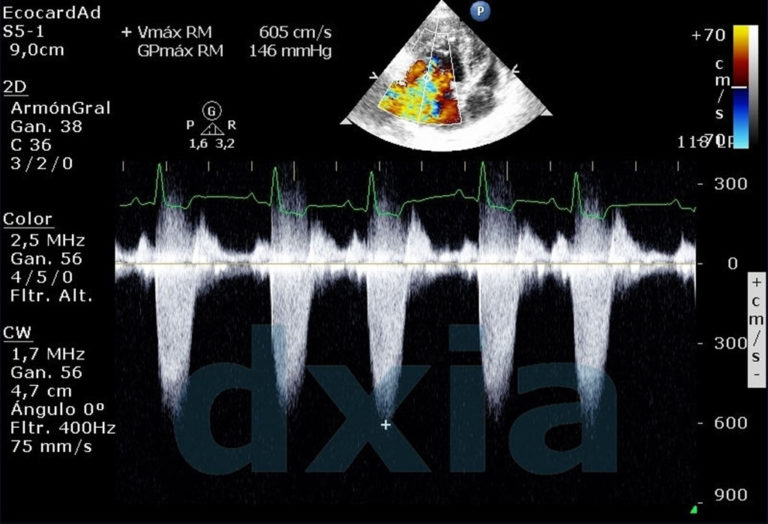

Ecocardiografía

Se recomienda la realización de Estudio Ecocardiográfico en una visita cardiológica rutinaria, pero sobre todo debe tenerse en cuenta su...